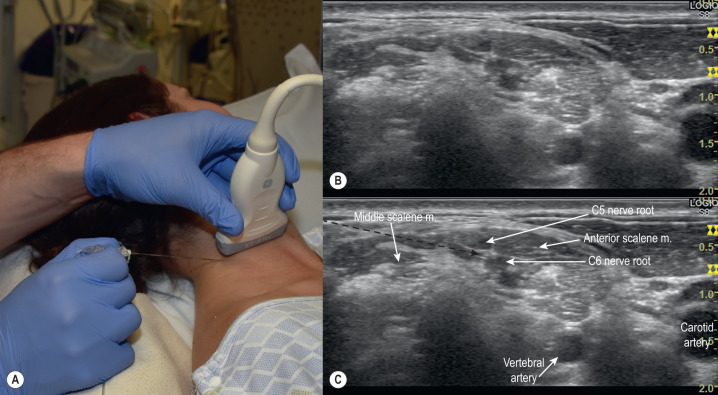

Intro: The interscalene block is performed at the level of the nerve roots, between the anterior and middle scalene muscles of the neck within the interscalene groove. Blockade of the brachial plexus at the interscalene level reliably blocks C5 to C7 nerve roots but frequently spares the ulnar nerve distribution, resulting in failure to block the ring and small fingers.

- 1.

Supine, back elevated 30 to 45 degrees with patient’s head turned away from block site. Consider positioning a pillow under the ipsilateral shoulder if needling area is limited.

Home Base:

Supraclavicular fossa. The nerve plexus and relevant vasculature are easily identifiable here by US. This is the same position as with a supraclavicular nerve block. Identify the subclavian artery and surrounding plexus, which appears as a “bunch of grapes.”

Scanning:

Slide the probe in the cephalad direction while keeping the nerve plexus in the center of the screen, holding the probe perpendicular to the skin.

The nerve plexus will begin to appear as discrete hypoechoic or dark circles between the scalene muscles.

Target:

Scan cephalad until the three distinct nerve roots are viewed stacked on top of one another within the interscalene groove. These are typically the C5 nerve root and two fascicles of C6.

Needling:

Advance the needle anteriorly toward the target. For safety, it is recommended to deposit the LA posteriorly to the plexus. It is not necessary to puncture between the dark circles.

The needle may be redirected above or below the target to obtain adequate spread.

Injection:

15 to 20 mL.

Unique side effects include Horner’s syndrome, hoarse voice from recurrent laryngeal nerve blockade, and ipsilateral hemi-diaphragmatic paresis from phrenic nerve palsy.

Lower volumes of LA and/or injecting posteriorly may reduce the incidence of phrenic nerve palsy.

Occasionally, the nerve roots may course through the scalene muscle (<5%). Target individual nerve roots if this is the case.

Be wary of neck vasculature traversing through the plexus. Use a Doppler if indicated to identify blood vessels.

The interscalene block spares the ulnar nerve distribution and proximal (above elbow) medial portion of arm near the axilla (intercostal-brachial nerve).